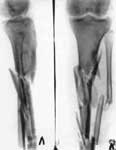

1.Results of traffic accident.

2.Defect after removal of medium/third of thing-bone.

3.Replacement of defect (24 centimeter) by means of Ilisarov's apparatus.

4.Results of treatment.